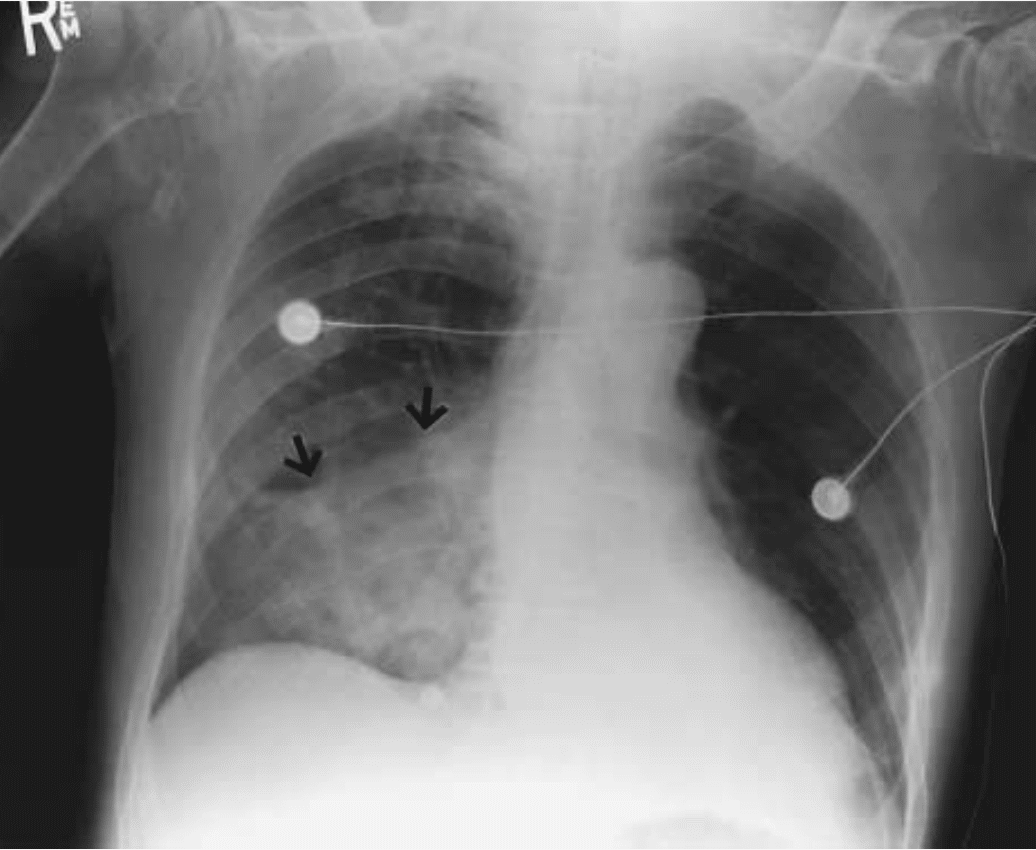

Air-Space Consolidation (Arrows) in the Right Lower Lobe in a

Patient Who Had Recently Had a Thrombotic Stroke. NEJM

- Changes: patchy opacities, usually gravity-dependent

- Most affected lobes:

- Right lower lobe (most common)